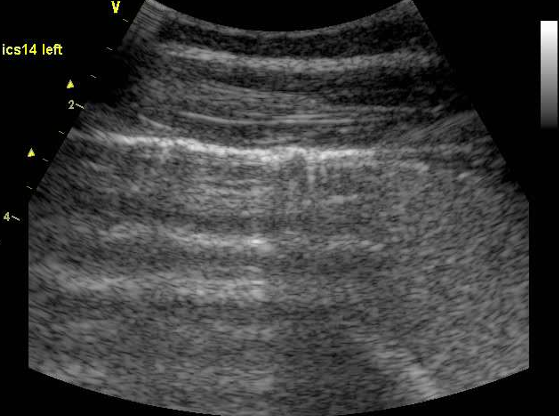

Ultrasound